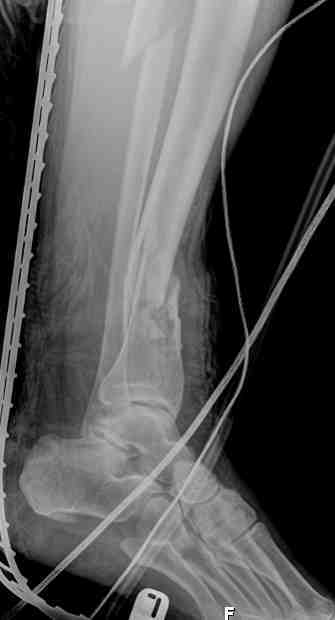

Выше представлены рентгенограммы открытого оскольчатого перелома нижней трети голени X-rays of Compound Comminuted # Distal/3 Lt Tibia

Операционные снимки перед и после наложения аппарата Илизарова In operation room before and after Ilizarov apparatus has been applied

Послеоперационные рентгенограммы Postoperative X-rays

В нижнем ряду представлены рентгенограммы после окончательной репозиции. And final reduction after Hexapod program has been finished